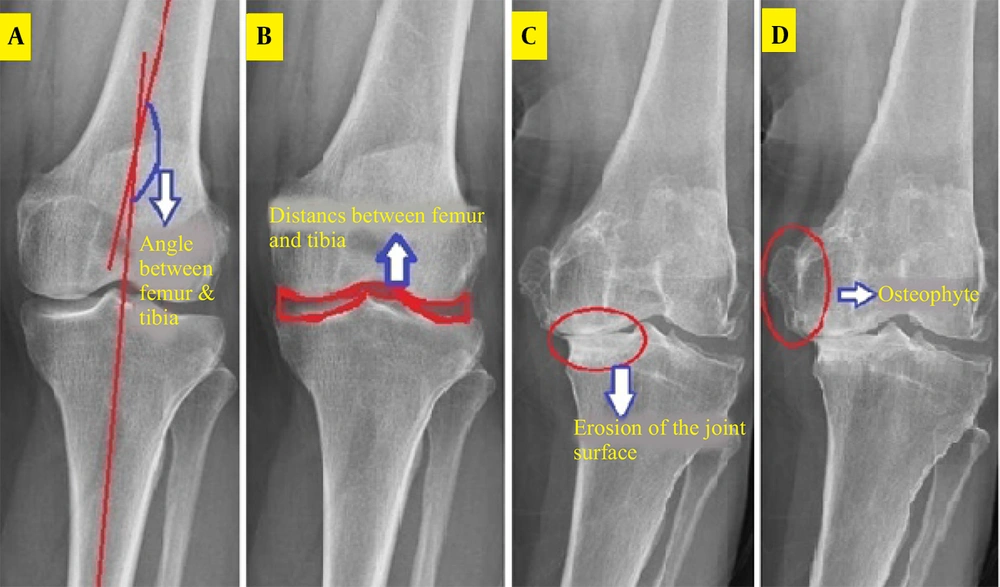

Four clinical features, aligned with the KL grading system and supported by prior studies, were extracted for osteoarthritis diagnosis (1, 3).

3.1. Femoral-Tibial Axis Angle

The femur and tibia curvature areas were segmented, and their centerlines drawn by connecting upper and lower points. The angle between these lines and the image horizon was calculated, with the difference (ranging from -8 to 8 degrees) indicating structural changes due to osteoarthritis (Figure 1). This was implemented in MATLAB as the TFA.M function.

3.2. Joint Space Width

The distance between femoral and tibial articular surfaces was measured in the middle knee region after cropping, contrast adjustment, and noise removal. The Otsu algorithm defined thresholds, and the Canny algorithm extracted horizontal joint space edges (Figure 1). Two vertical distances were measured, and their ratio (0 - 1) quantified joint space narrowing, implemented as JSW.M.

3.3. Subfemoral Bone Surface Erosion

A region between the femur and tibia was analyzed, with brightness intensity serving as an indicator of cartilage and bone erosion (Figure 1). Eroded areas, appearing brighter, yielded contrast values (100 - 250), normalized by dividing the standard deviation by the contrast to produce a 0 - 1 range, recorded as SCL2. M.

3.4. Osteophyte Detection

The knee joint was analyzed for bony outgrowths. A morphological gradient image highlighted vertical edges, and the Otsu method produced a binary image (Figure 1). The ratio of area to perimeter of prominent regions (initially 1 - 2) was normalized to 0 - 1 by subtracting one, saved as OST4. M.

In this study, four clinical features related to knee osteoarthritis were extracted from knee radiographs: The angle between the femoral and tibial axes, the joint space distance, the amount of subarticular erosion, and the osteophyte assessment. To convert these clinical features into processable numerical values, image processing-based approaches were applied, and each feature was defined as a normalized scalar in the range [0,1].